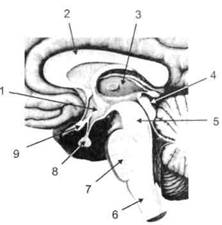

Головной мозг (рис. 6 и 7) анатомически ограничен костными структурами черепа и структурно делится на задний, средний, промежуточный и передний.

Задний мозг состоит из продолговатого мозга, мозжечка и моста (варолиева) (рис. 8 и 9). Продолговатый мозг анатомически является продолжением спинного, хотя по внутренней структуре и соотношению серого и белого

Рис. 8. Средне-нижние отделы головного мозга: J — зрительная хиазма; 2 — латеральное коленчатое тело; 3 — медиальное коленчатое тело; 4 — подушка таламуса (фрагмент); 5 — бугры четверохолмия; 6— мозжечок; 7— спинной мозг; 8 — продолговатый мозг; 9— варолиев мост; 10— ножки мозга; // — гипофиз

Рис. 9. Средне-нижние отделы головного мозга (срез): / — гипоталамус; 2 — мозолистое тело; 3 -таламус; 4— бугры четверохолмия; 5- ножки мозга; 6— продолговатый мозг; 7-варолиев мост; 8— гипофиз; 9— зрительная хиазма

Промежуточный мозг (диэнцефальный) включает в себя два отдела — зрительный бугор (таламус) и подбугорную область (гипоталамус) (рис. 9).

Гипоталамус представляет относительно узкий слой мозговой ткани, расположенный в промежутке между зрительным бугром и разрывом ножек мозга. В нем расположены многочисленные высокодифференцированные ядра, регулирующие температуру тела, аппетит, водный баланс, углеводный и жировой обмен, сосудистый тонус и другие вегетативные функции, связанные с обменом веществ, в том числе с нейро-гуморально-гормональным контролем. Здесь же находятся центры, осуществляющие регуляцию сна, сексуального и эмоционального поведения. Гипоталамус играет важнейшую роль в регуляции гомеостаза (постоянства внутренней среды организма), но, помимо решения физиологических задач, проявляет себя и в качестве:

Кроме того, к структурам гипоталамуса анатомически относят гипофиз — железу внутренней секреции и зрительную хиазму — место неполного перекрестья зрительных нервов (рис. 8 и 9).